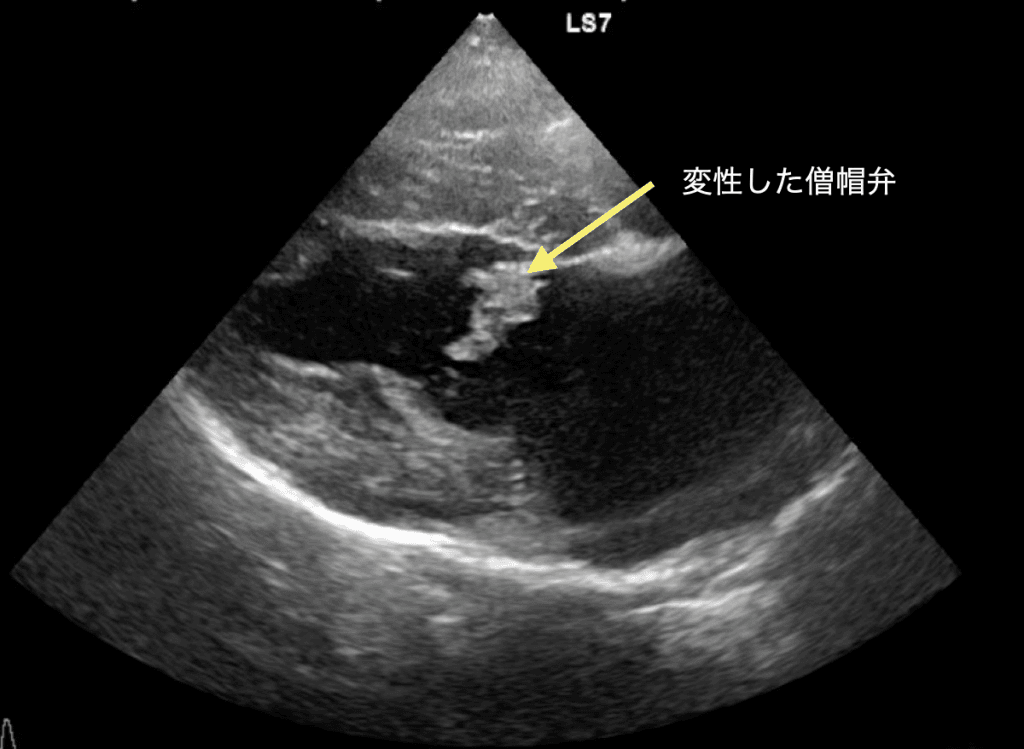

犬の心疾患で最も多い『僧帽弁閉鎖不全症』。

心臓の左心房と左心室の間にある「僧帽弁」というドアが、加齢とともに分厚く変形し、ピタリと閉まらなくなる病気です。弁が完全に閉まらないため、血液が逆流し、心臓や肺に大きな負担がかかります。進行すると肺水腫(肺に水が溜まる状態)を引き起こし、呼吸困難に陥る命に関わる疾患です。肺水腫は突然起こるものなので、昨日まで元気だったのに、急に呼吸がしづらそう・・なども十分に起こりうる疾患です。

初期段階では症状がほとんど出ないため、聴診での心雑音のチェックが最初の入り口となります。聴診で心臓の雑音が確認された場合は、レントゲン検査、心臓超音波(エコー)検査、心電図、血圧測定などを行い、心臓の拡大や逆流の程度を正確に評価します。